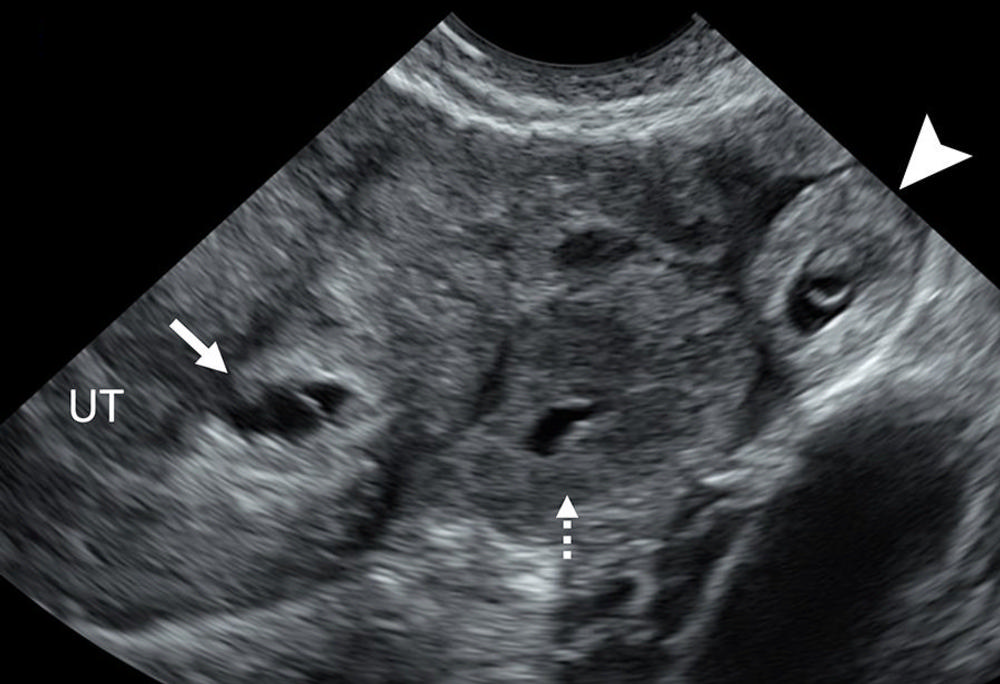

Figure 8. Heterotopic pregnancy. Transvaginal transverse grayscale US image in a 27-year-old pregnant patient shows an early intrauterine pregnancy (IUP) (solid arrow) containing a yolk sac and a tubal ring of ectopic pregnancy (EP) (arrowhead) also containing a yolk sac. The coexistence of an IUP and EP is termed heterotopic pregnancy. The left ovary contains a corpus luteum (dotted arrow) and is seen in the center. The rim of chorionic tissue in the IUP and EP is hyperechoic, whereas in contrast, the corpus luteum is hypoechoic. Echogenicity can help distinguish a tubal ring from a corpus luteum in some cases. UT = uterus.

High-res (TIF) version